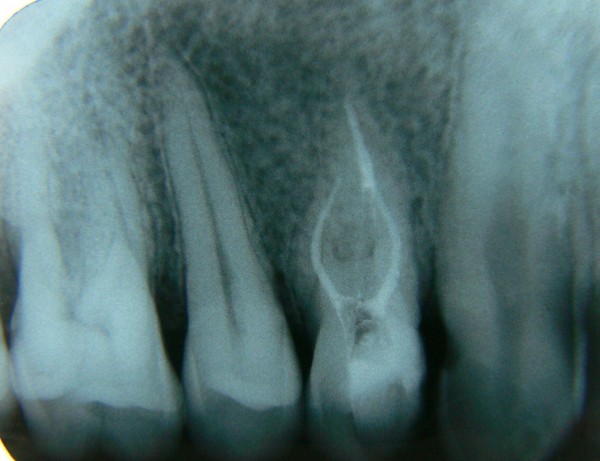

Examenul radiologic , ca metoda complementara de investigatie, este indispensabila în diagnosticul si terapia afectiunilor endodontice, atat la inceputul, cat şi pe parcursul tratamentului endodontic propriu-zis. De asemenea, urmărirea evoluţiei cazului, în timp, nu este posibilă fără examenul radiologic. În acest sens, cea mai uzuala este radiografia retroalveolara care ne furnizeaza informatii precise si in ultimii ani a aparut si CBCT - cone beam computer tomography.

În mod uzual sunt necesare 3-4 radiografii dentare mici (retroalveolare), înainte de tratament, în timpul şi imediat după finalizarea acestuia. Uneori, cazurile mai dificile (numar mare de radacini, instrumente rupte in canale, canale inguste, calcifiate, cai false,etc) pot necesita un număr suplimentar. Aparatura radiologică performantă utilizată în prezent expune pacientul la o doză de radiaţii mult redusă, care nu afectează sănătatea acestuia.